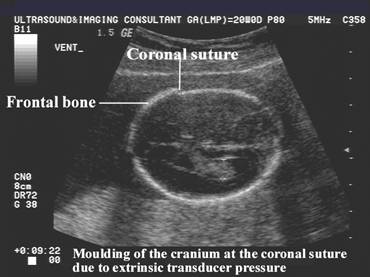

Moulding and overlap of the cranium sutures may occur in:

Extrinsic transducer pressure.